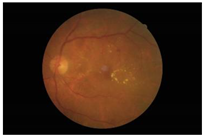

Figure 4.

Example of DDR dataset: (a) normal; (b) NPDR; (c) PDR.

In this study, we used the Dataset for Diabetic Retinopathy (DDR) dataset [13], one of the fundus image datasets that became available to the public in 2019. This relatively new dataset contains 13,673 fundus images from 9598 patients collected from several hospitals in China in 2016–2018. DDR fundus images were collected from several different camera types using single-view and captured using the same technique. It consists of six categories, such as normal (6266 data), mild NPDR (630 data), moderate NPDR (4477 data), severe NPDR (236 data), PDR (913 data), and the undegradable images with poor quality (1151 data). It should be noted that classes are very unbalanced in the DDR datasets. The classification of unbalanced classes is challenging due to the highly skewed distribution of classes and the unequal costs of misclassification. Li, Gao, Wang, Guo, Liu, and Kang [13] state that lesions on the fundus image of mild NPDR are difficult to identify, and some severe NPDR classes are also easily misclassified as moderate NPDR. Therefore, we balanced this dataset by re-sampling using only three classes: normal, NPDR (mild, moderate, and severe classes were combined into one class), and PDR. Then, each class contains 913 data points, adjusting the amount of data in the PDR class with the distribution of training, validation, and testing data as described in Table 1. A sample of the DDR dataset is presented in Figure 4. It can be seen that there are no DR lesions on the normal retina. Retinal signs of NPDR can be observed in the presence of lesions, such as exudates, MAs, and HAs. Meanwhile, new blood vessels form in the retina affected by PDR (advanced DR cases).